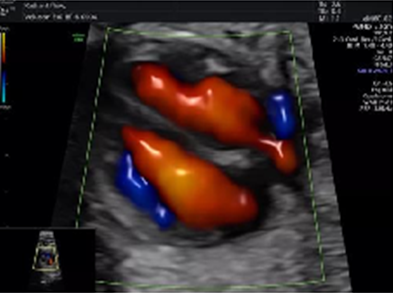

心臟超聲檢測(cè)更立體評(píng)估更準(zhǔn)確

具備一整套胎心成像技術(shù),支持從胎兒心臟結(jié)構(gòu)到心功能的分析,是胎兒心臟檢測(cè)評(píng)估領(lǐng)域的技術(shù)指導(dǎo)。雙平面成像技術(shù)可真實(shí)呈現(xiàn)胎心結(jié)構(gòu)、臍帶、血流變化,是目前超聲領(lǐng)域診斷的利器。